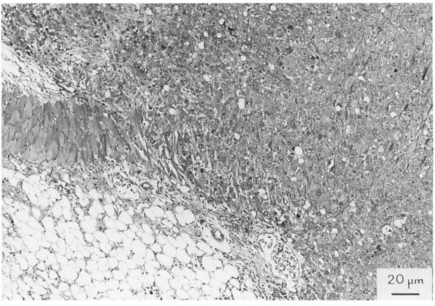

将MKN-45细胞皮下移植到裸鼠体内后,MKN-45异种移植物显示侵袭性生长到宿主动物的皮下肌肉。

图片

无胸腺裸鼠皮下MKN-45肿瘤[1]